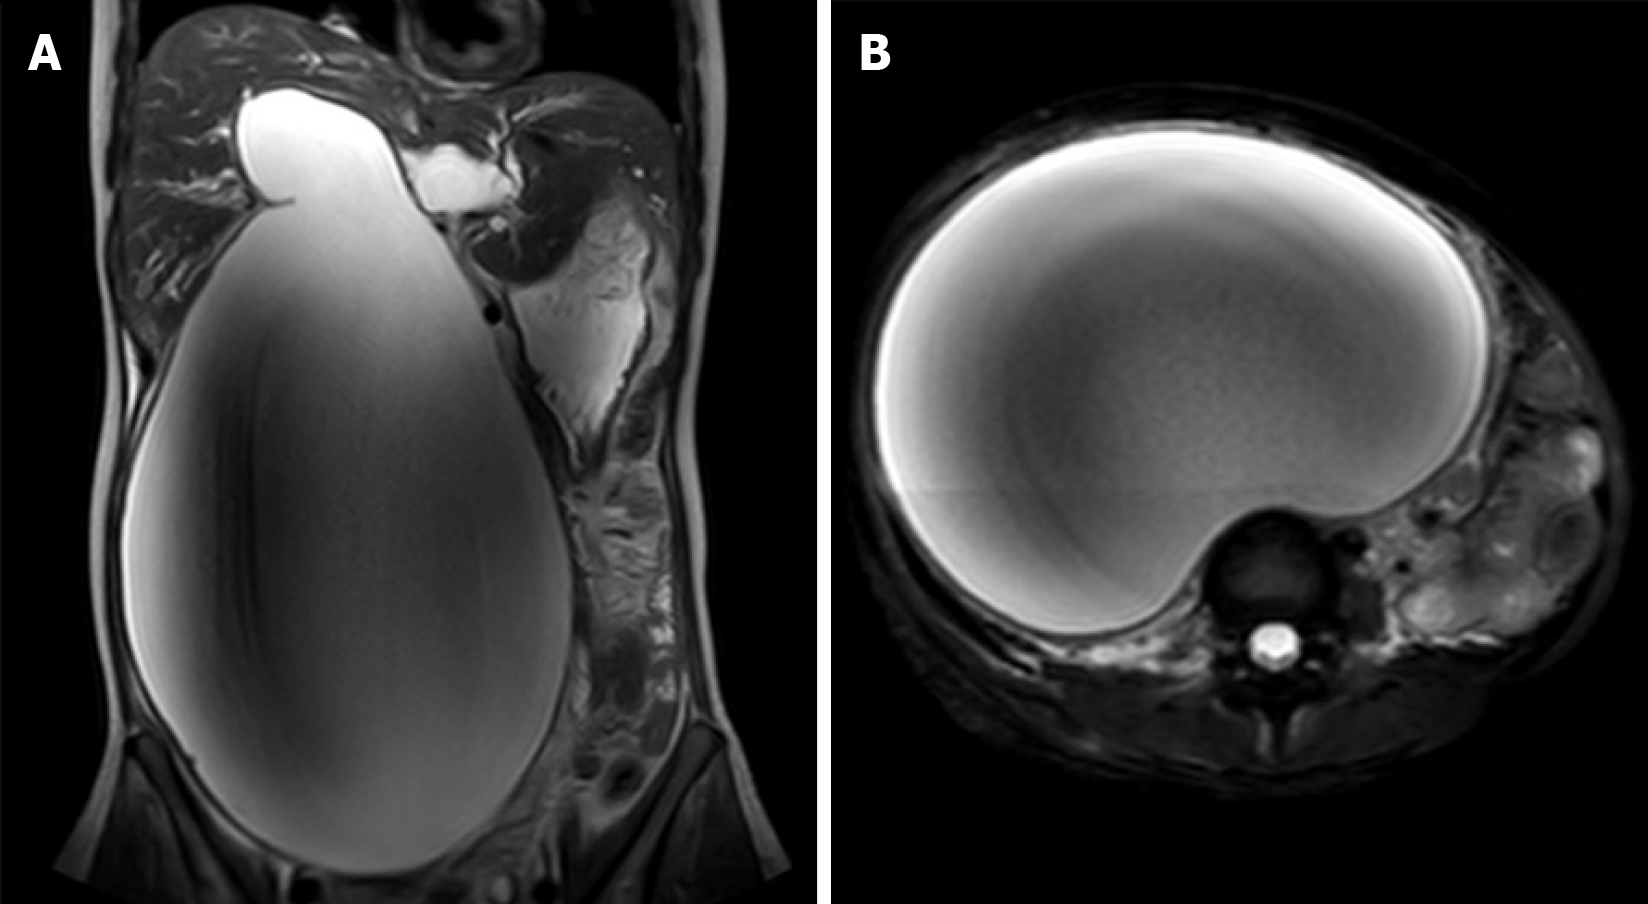

Upon admission, the patient underwent magnetic resonance imaging and magnetic resonance cholangiopancreatography (MRCP), which identified a giant cystic lesion in the abdominal cavity, measuring approximately 338.05 mm × 194.66 mm × 131.61 mm (Figure 1). Multiple calculi were observed at the cyst base (Figure 2A). Moreover, MRCP confirmed cystic dilatation of the common bile duct and intrahepatic biliary ducts, accompanied with hydronephrotic dilatation of the renal pelvis (Figure 2B), which was caused by ureteral compression by the cyst. The gallbladder was atrophic as a function of impaired bile storage and secretory function (Figure 2C). Diffusion-weighted imaging sequences (Figure 2D) revealed layering of the cystic contents, suggesting biliary sludge sedimentation. Following the classification guideline of Todani et al[8], the choledochal cysts were classified into five types. Type I is more prevalent in pediatric populations, whereas type IV (subclassified as IV-A in this case) is frequent among adults[9]. The patient in this case was diagnosed with a type IV-A choledochal cyst.